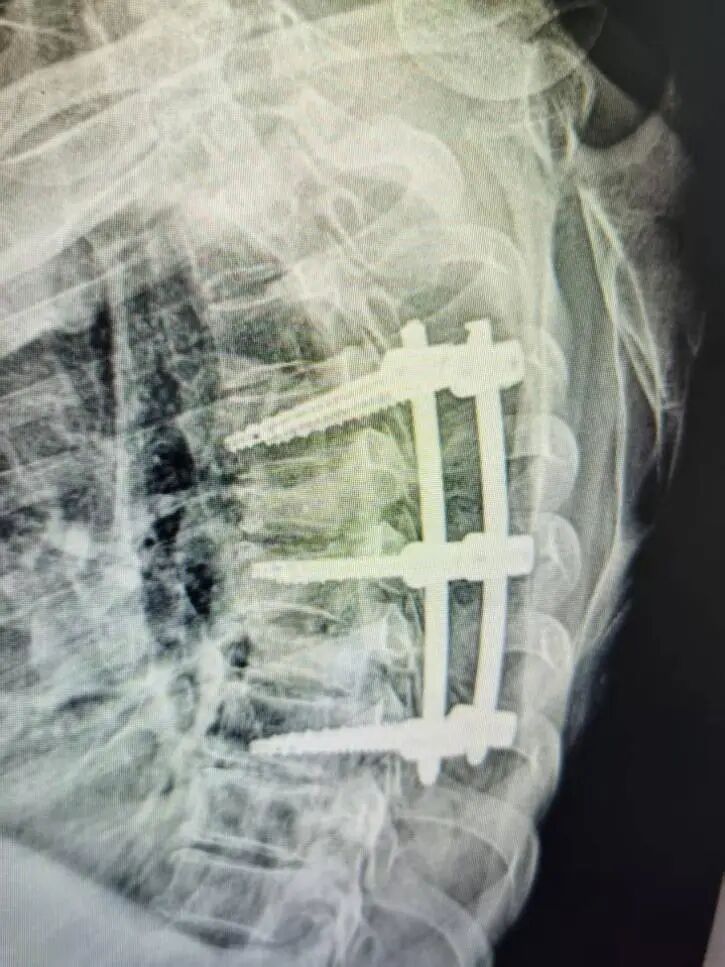

签约仪式后,朱卉敏教授团队立即开展手术演示。手术针对一名多发胸椎椎体骨折患者。一直以来,胸椎尤其是高位胸椎手术因解剖结构复杂、毗邻脊髓与大血管,稍有不慎,极易损伤神经导致瘫痪,容错率几乎为零,向来是脊柱外科的“禁区”与难点,令无数医师畏之如虎、知难而退。

朱卉敏教授团队一边操作,一边为现场观摩的福鼎市医院骨科团队详细讲解解剖标志、操作要点与风险规避技巧。手术过程流畅、视野清晰、出血极少,历时约50分钟,手术顺利完成。术后患者即刻苏醒,次日即可下床活动,疗效显著获得在场医护人员与患者家属的高度赞誉。